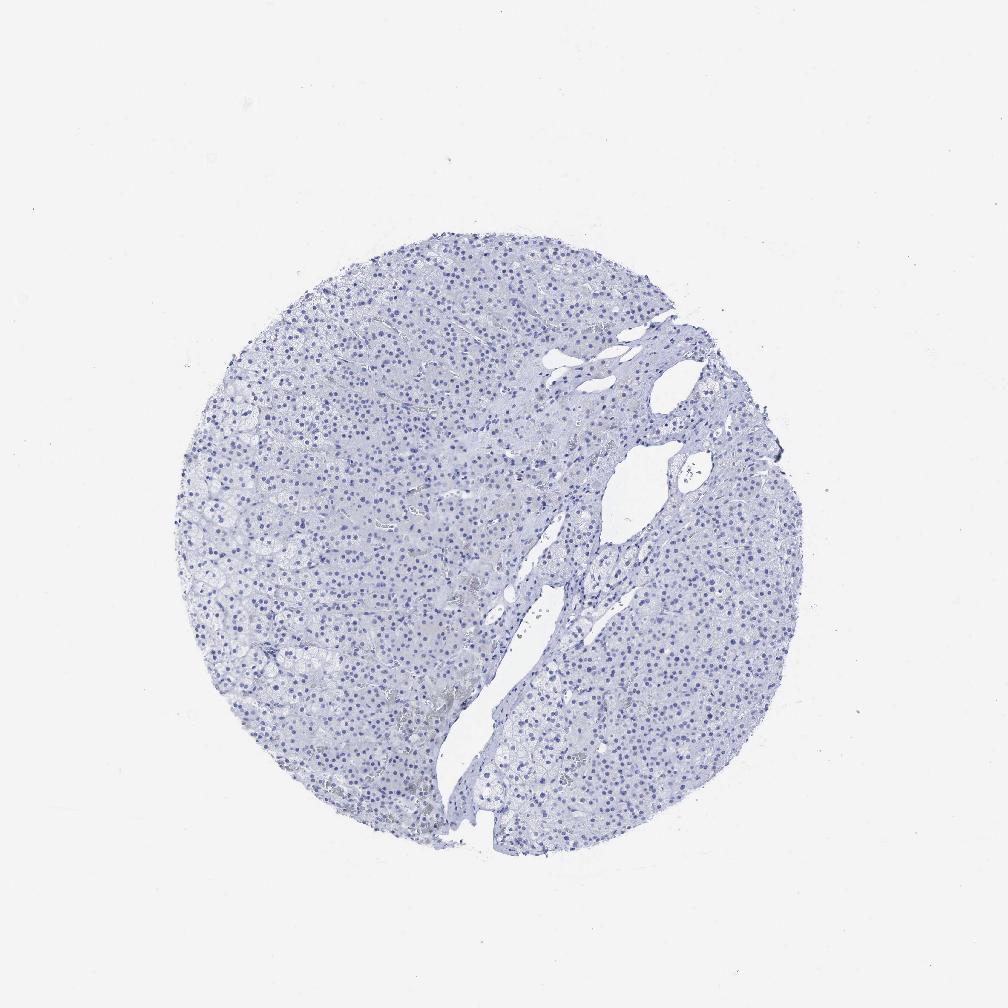

ADRENAL GLAND - Antibody stainingi

Antibody staining in the annotated cell types in the current human tissue is reported as not detected, low, medium, or high, based on conventional immunohistochemistry profiling in selected tissues. This score is based on the combination of the staining intensity and fraction of stained cells.

Each image is clickable and will lead to virtual microscopy that enables deeper exploration of all samples and also displays staining intensity scores, fraction scores and subcellular localization as well as patient and tissue information for each sample.

Antibody HPA011041Antibody HPA019758Antibody CAB000021Antibody CAB000022

Glandular cells Not detectedLowNot detectedNot detected